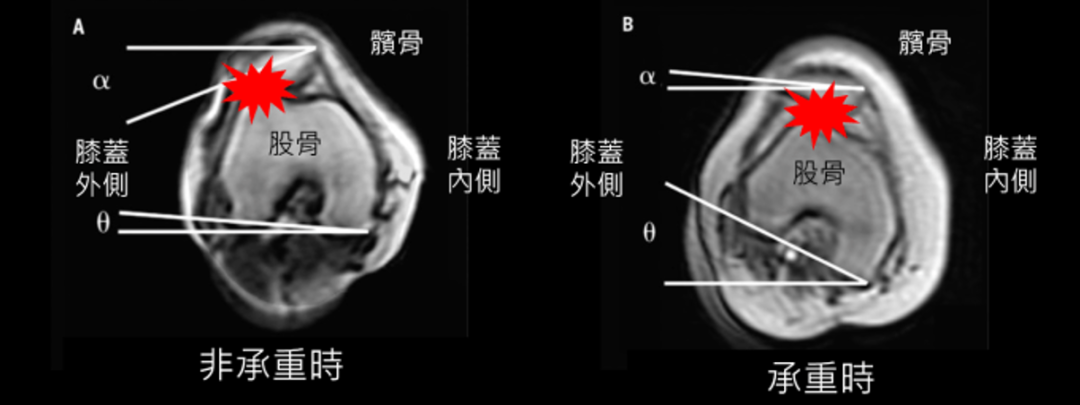

下面这张图有很好的注解

(这张图是站姿下从膝盖往下看髌骨的样子)

承重时(站起来或蹲膝盖承受重量时)的,股骨的向内旋转,这时侯髌骨依然在正前面。然而当坐下来或是躺下来等非承重状态时,股骨向前,髌骨就被带到往外我们常看髌骨外翻的样子,这样长期摩擦也会产生疼痛,那下个问题是:为什么膝盖会内扣?